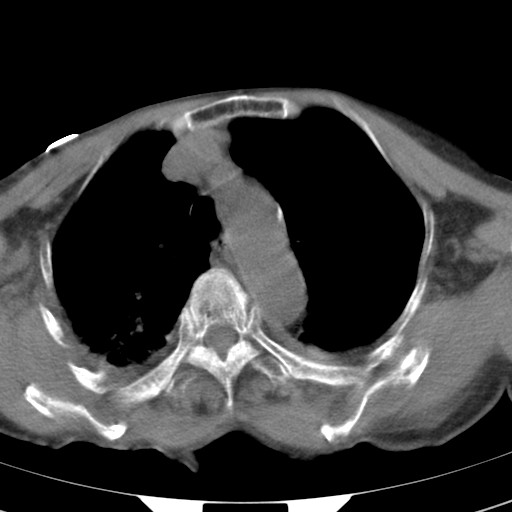

标题: CT21467:女,93岁,摔伤后检查。

女,93岁,摔伤后检查。

右肺炎症,心功能不全伴双侧胸腔积液,右下肺膨胀不全,食管裂孔疝,冠脉钙化,心包少量积液,左侧肋骨骨折,请上传骨窗.

右侧锁骨\\肩胛骨骨折、右侧湿肺,心功能不全伴双侧胸腔积液,右下肺膨胀不全,左膈破裂或食管裂孔疝,冠脉钙化,心包少量积液,请上传骨窗.

右肺炎症,心功能不全伴双侧胸腔积液,右下肺膨胀不全,食管裂孔疝,冠脉钙化,心包少量积液,左侧肋骨骨折,右肩甲骨粉碎性骨折。93岁,高寿哇!